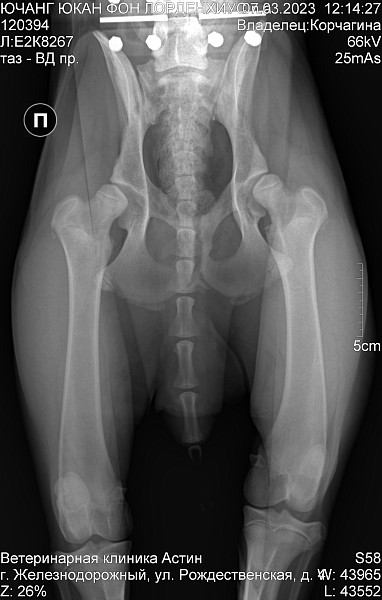

Немецкая овчарка. Кобель.

Др 29 07 2022

С первого дня дома бегал как заяц, на первых прогулках подтвердился такой бег. С трудом встаёт, перенося вес на передние лапы. Хромает спустя 10 минут прогулки.

Врачи в городе не дают внятных ответов и заключений. Хочется узнать имеется ли на снимке дисплазия?

Добрый день. Двустороння дисплазия тазобедренных суставов. Рекомендован прием ортопеда и имплантация суставов